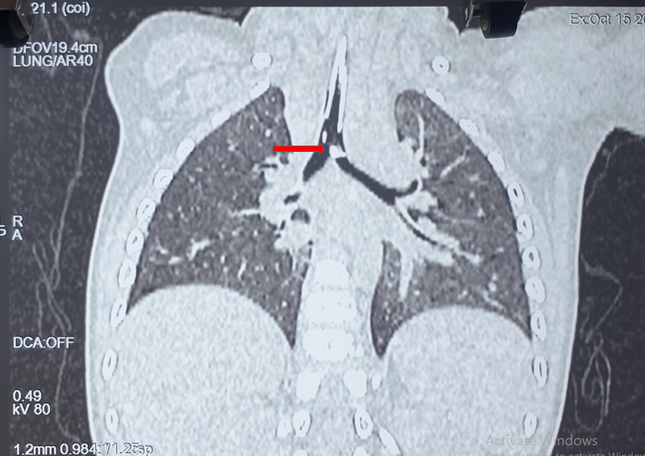

Kết quả chụp CT-Scan phổi cho thấy có dị vật kích thước lớn (0,5x1cm) nằm ở ngay vị trí chia đôi khí quản thành phế quản gốc bên phải và trái. Các bác sĩ đã hội chẩn liên chuyên khoa và quyết định thực hiện nội soi đường thở cấp cứu cho bệnh nhi. Dị vật là một mảnh xương sắc nhọn ghim vào thành phế quản đã được ê kíp bác sĩ gắp ra ngoài thành công. Hiện, bệnh nhi đang được điều trị tại khoa Hồi sức Ngoại, tình trạng sức khỏe dần bình phục.